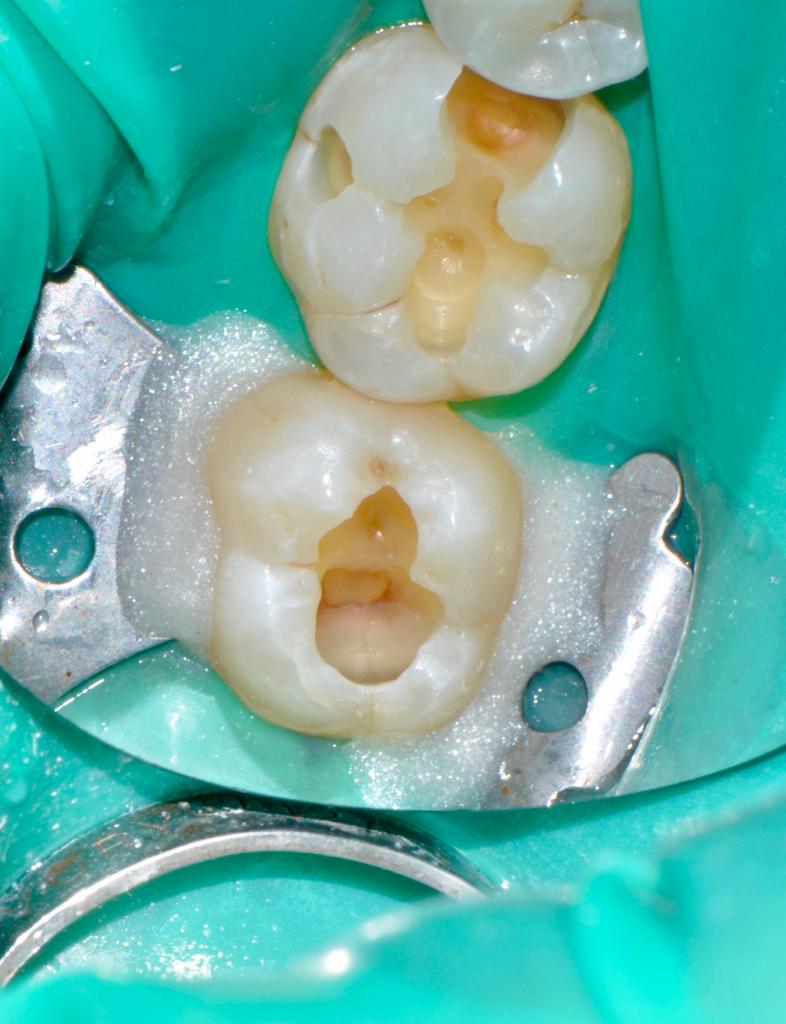

Alcuni casi clinici